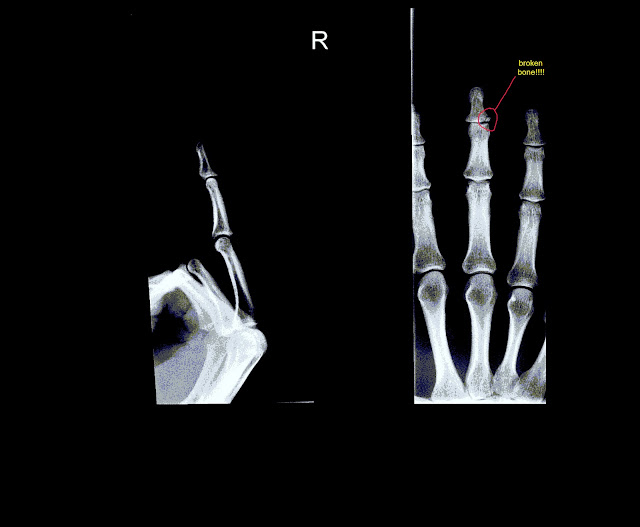

השבוע כבר התייאשתי,כבר סוף יולי עברו 5 חודשים ועדיין לא עברו הכאבים, החלטתי כמובן שמשהו לא בסדר והלכתי לעשות X-RAY (מעט מאוחר מידי…)

התוצאה לפניכם:

יש לי שבר!!

מסתבר שהקרע בעור וכל הבלגאן הסתיר מתחתיו שבר באצבע , וכול הזמן הזה טיפסתי עם אצבע שבורה!!!

עכשיו אין הרבה מה לעשות כי התחיל איחוי , ואין טעם לקבע.

גורם לך לחשוב כמה גוף האדם מסוגל לשאת וכמה רזרבות יש לנו.